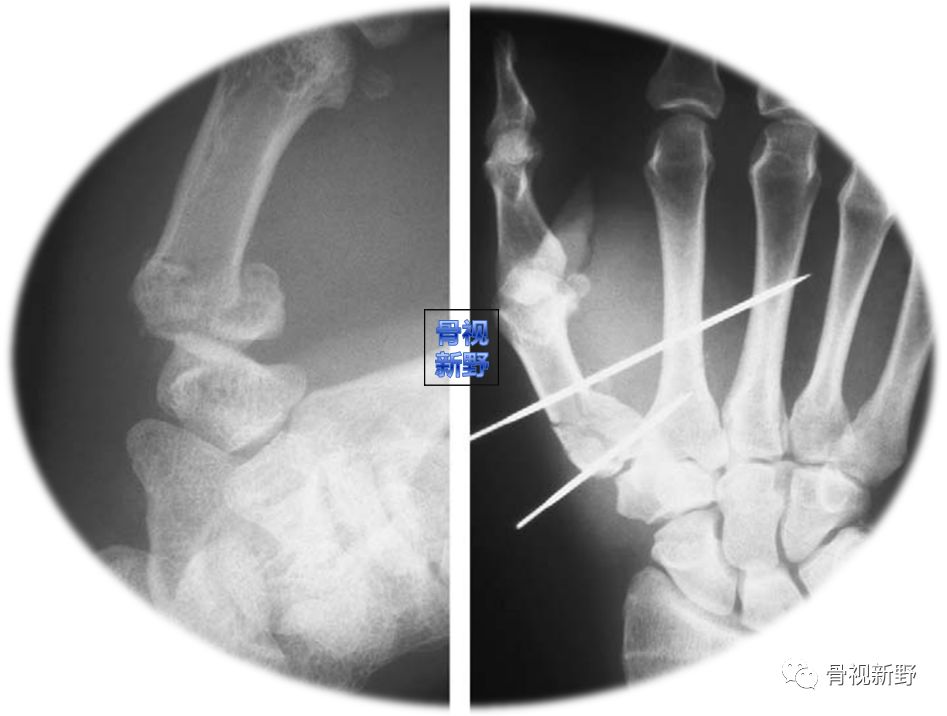

case1

case 2

经皮双针交锁固定可防止退针、维持骨折的复位及拇指的外展对掌位。